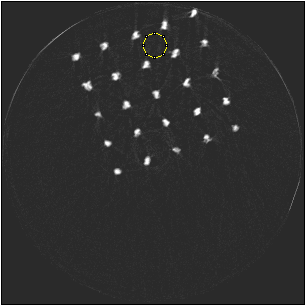

Figure 5 illustrates a single slice spectral reconstruction of the Ti scaffold. Varying levels of streak artefacts can be seen across the spectral reconstructions. The spectral reconstructions for the energy ranges 35 to 80 keV, 55 to 80 keV, and 62 to 80 keV shown in figure 5, exhibit reduced streak artefacts. A region-of-interest (ROI) analysis was performed in the immediate vicinity of the metal region where the streaks are more pronounced. Average attenuation coefficent of air close to zero conveys less regional noise/artefacts. The regional average attenuation coefficient (μROIsubscript𝜇𝑅𝑂𝐼\mu_{ROI}) of the non-metal (air) region in 55 to 80 keV reconstruction (figure 5c) shows reduced artefacts. Even though minor streaks and statistical noise appear in figure 5d due to photon limitation, the artefacts are less pronounced in comparison to the wide energy acquisition in figure 5a.

Refer to caption

(a) 15 to 80 keV

(b) 35 to 80 keV

(c) 55 to 80 keV

(d) 62 to 80 keV

Figure 5: Single slice spectral reconstruction of Ti scaffold sample. μROIsubscript𝜇𝑅𝑂𝐼\mu_{ROI} is 0.246, 0.030, 0.008 and 0.103 for the circular ROI in (a), (b), (c) and (d) respectively.